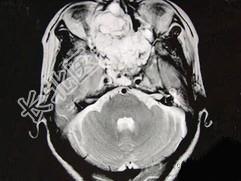

- 单项选择题女性,41岁, 鼻腔流脓涕3年,鼻部面部肿胀1年, 近来加重,MRI检查如图, 请选择最可能诊断 ( )

A、鼻腔内囊肿

B、鼻腔内出血

C、鼻腔软骨瘤

D、鼻咽癌

E、鼻腔血管瘤